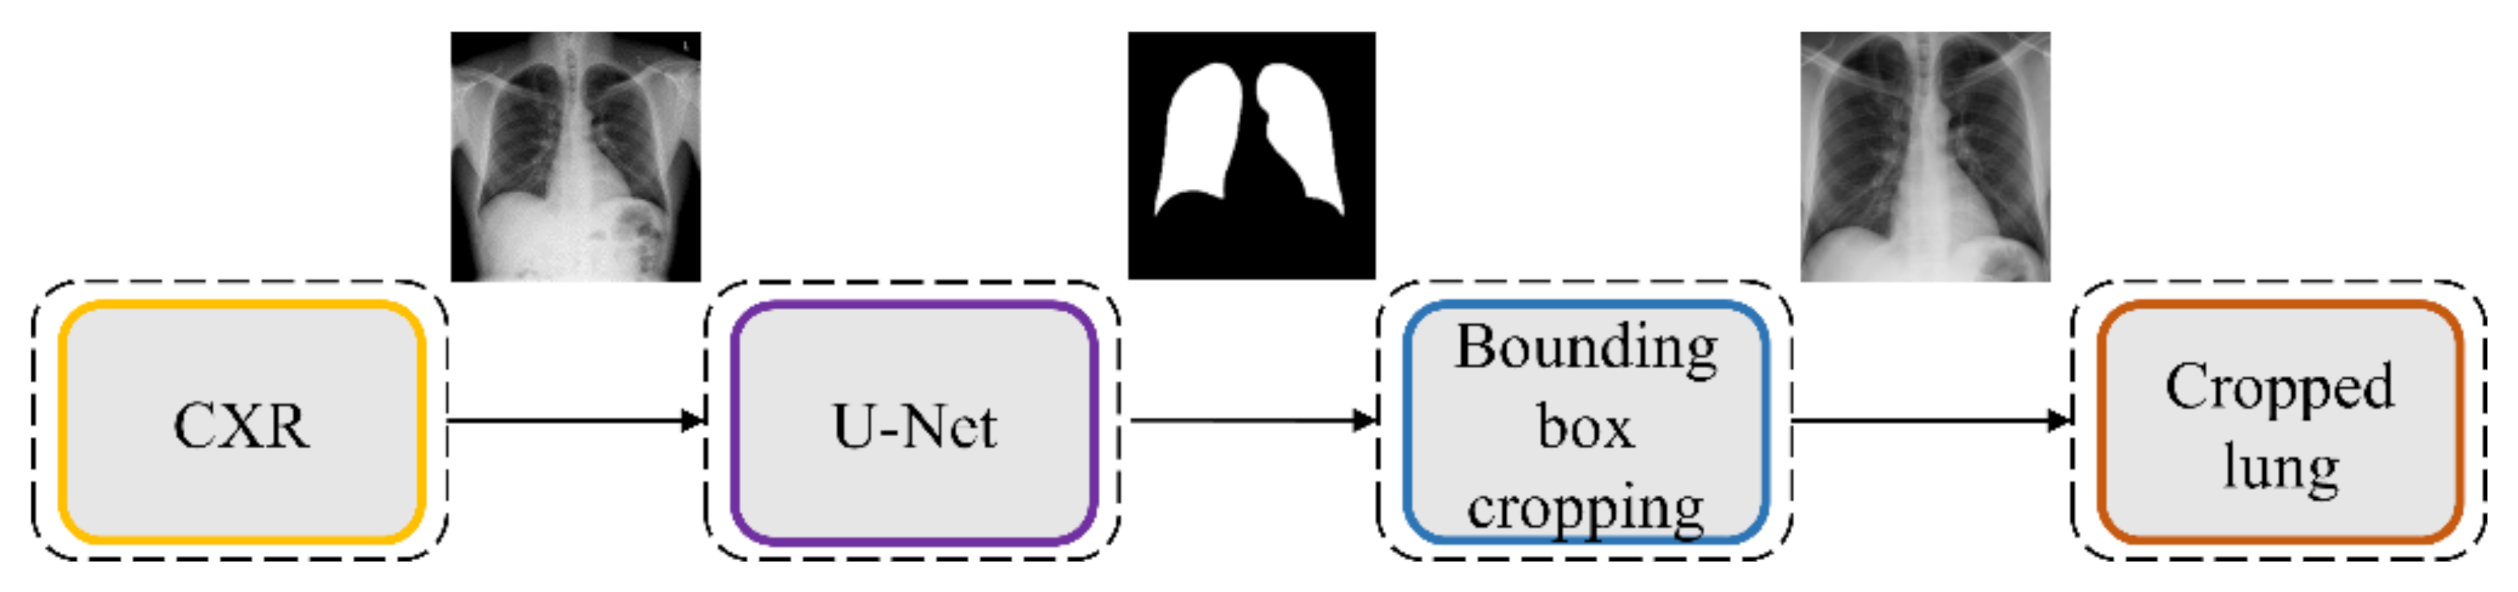

2.4. Lung Segmentation and Preprocessing

The performance of DL models is severely impacted by data quality. Irrelevant features may lead to biased learning and suboptimal model performance. The task of detecting TB or other pulmonary disease manifestations is confined to the lung regions. Thus, regions in CXRs other than the lungs are irrelevant to be learned by the models. Hence, it is crucial to segment the lung regions and train the lung ROI models to help them learn relevant features concerning normal lungs or other pulmonary manifestations.

The U-Nets are one of the most powerful CNN models that are used for precise and accurate segmentation of medical images [

We evaluated the segmentation performance of the VGG-16-CXR-U-Net and VGG-19-CXR-U-Net models and other SOTA U-Net variants, including the standard U-Net, V-Net with ResNet blocks, improved attention U-Net, ImageNet-pretrained VGG-16 U-Net, and VGG-19-U-Net toward lung segmentation.

Figure 4 illustrates the lung segmentation workflow.

The models are trained on a publicly available collection of CXRs and their associated lung masks [

40]. We allocated 10% of the training data with a fixed seed value for validation. We introduced variability into the training process by augmenting the training input with random affine transformations, including horizontal flipping, height and width shifting, and rotations. The trained models are tested with the cross-institutional Montgomery TB CXR collection and their associated GT lung masks [

6]. We emphasize that such an evaluation with a cross-institutional test collection would provide a faithful performance measure since the test data have varying visual characteristics and are completely unseen during model training, thereby preventing data leakage and ensuring generalization.

The best performing model is used to generate lung masks at 256 × 256 spatial resolution. The generated lung masks are overlaid on the original CXR images to demarcate the lung boundaries and then cropped into a bounding box encompassing the lung pixels. We preprocessed these images by (i) resizing the cropped bounding boxes to 256 × 256 spatial resolution, (ii) improving contrast by saturating the bottom and top 1% of all image pixel values, (iii) normalizing the pixel values to the range (0–1), and (iv) performing mean subtraction and standardization such that the resulting distribution has a mean µ of 0 and a standard deviation σ of 1 as shown in Equation (1):